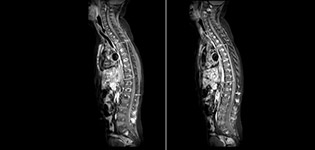

Philips mDIXON TSE is a two-point DIXON technique that separates water and fat signals, for time-efficient fat-free imaging, even in challenging neuro anatomy.

“mDIXON TSE has been one of the most significant improvements in imaging sequences that we have utilized to date at PCH,” says Dr. Miller. “Its multi-parametric acquisition allows us to obtain fat suppressed images and equivalent non-fat suppressed T2 images all in the same sequence. In addition, prior methods of fat suppression could be artifactually corrupted by poor patient anatomy or poor operator application, but with mDIXON we now have a robust and reliable method of fat suppression.”

Fat saturation is historically challenging at the ends of fields of view, especially in total spine imaging and in difficult patient anatomy such as the lower regions of the neck. “Due to the unique fat suppression capabilities of mDIXON, however, these challenges no long apply,” says Dr. Miller. “We routinely obtain homogeneous fat suppression under virtually all conditions. It has also led to some efficiencies by not having to repeat sequences because of that technical failure.”

mDIXON TSE makes a difference

“mDIXON TSE is most useful in patients with lesions or abnormalities in the soft tissues such as the face and neck, and for patients with contrast enhancing abnormalities that are mostly visible with fat suppression,” says Dr. Miller. “All our spine imaging now routinely contains mDIXON water-only T2 images, and this allows us to identify pathology that may be obscured by non-fat suppressed imaging such as injuries of the bone. And it’s not necessary to obtain additional standard TSE T2 images because the in-phase mDIXON images are equivalent to standard TSE T2 images.”

“mDIXON TSE has increased our diagnostic confidence in ruling in or ruling out abnormalities in which fat suppression is critical to diagnosis, such as metastatic disease or osseous abnormalities.”